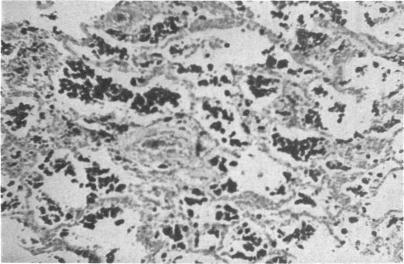

Association of cardiac pulmonary haemosiderosis and fibrosis.